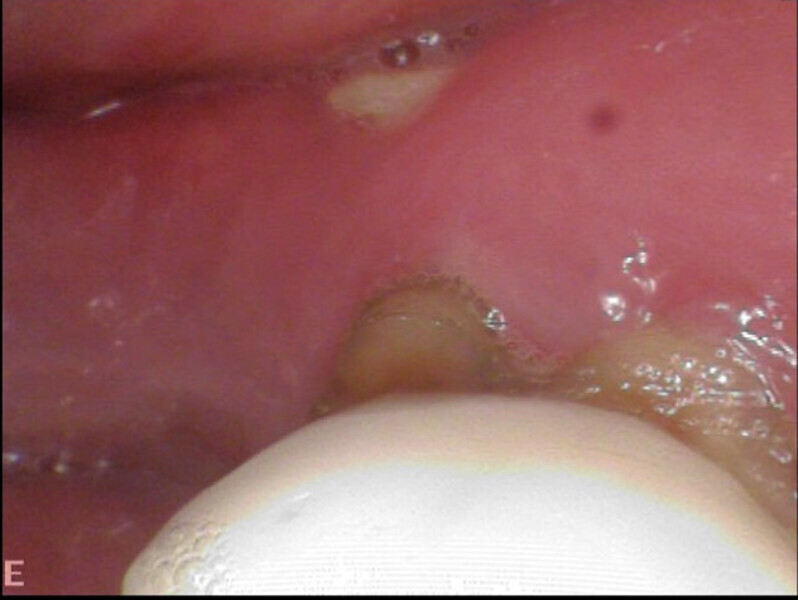

Our recommendations were a loading dose of antibiotics for ten days, followed by retreatment of the molar and antibiotics for five days. Unfortunately, her primary dentist ended up extracting the molar, the socket never healed and osteonecrosis of the jaw was established (Fig. 9). At this point, our recommendation was to have her treating doctor discuss treatment of this area with a maxillofacial specialist.

Figs. 9a & b: Osteonecrosis after extraction of the mandibular first molar.